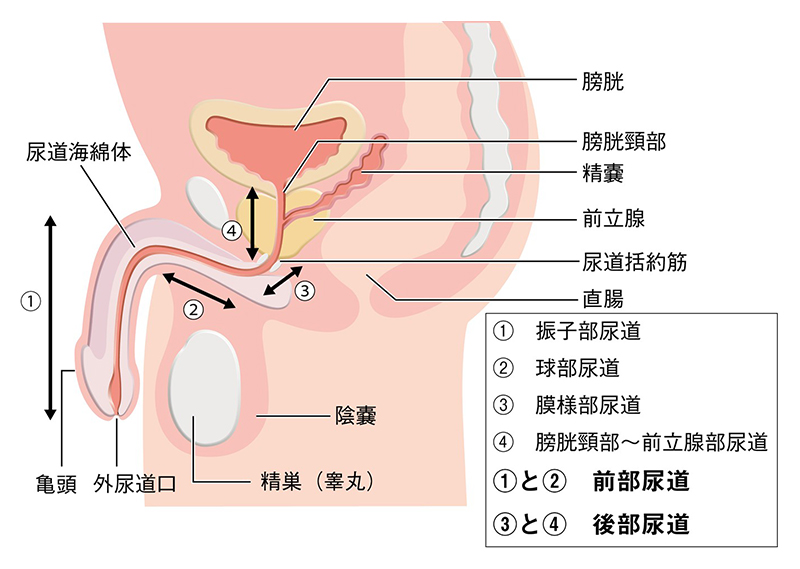

前立腺炎の場合、一般的には会陰部(肛門の前)の鈍痛、 睾丸の鈍痛、排尿痛があげられます。 そして、前立腺炎では多くの場合、この会陰部に痛みが生じます。 会陰部の痛み 急性前立腺炎の場合 急性前立腺炎の場合は、高熱と会陰部痛をともなうため、 男性 会陰部にしこり person 30代/男性 前も相談させて頂きました。 だんなが睾丸のすぐ下から肛門の間にしこりを発見しました。 去年には肛門周囲膿瘍で入院したこともあり、診察を受けに行きましたが、経過は大丈夫で、しこりについては1919 男性 男性の尿道は長く、外尿道口から入った細菌は、膀胱に達する前に排尿によって流されることが多い。前立腺からの分泌液には、細菌の侵入を防ぐ働きがある。 女性 女性は、男性に比べて、尿道が短い上、肛門や膣前庭部と外尿道口が近いので、その分、細菌が膀胱の中に入りやすい。

尿道狭窄症とは 堀口明男 Official Site

生殖器の構造 看護roo カンゴルー

尿道狭窄症とは 堀口明男 Official Site

尿道形成術とは 堀口明男 Official Site

男性の生殖器系の構造 21 男性の健康上の問題 Msdマニュアル家庭版

生殖器系 からだのしくみを調べる 医療総合qlife